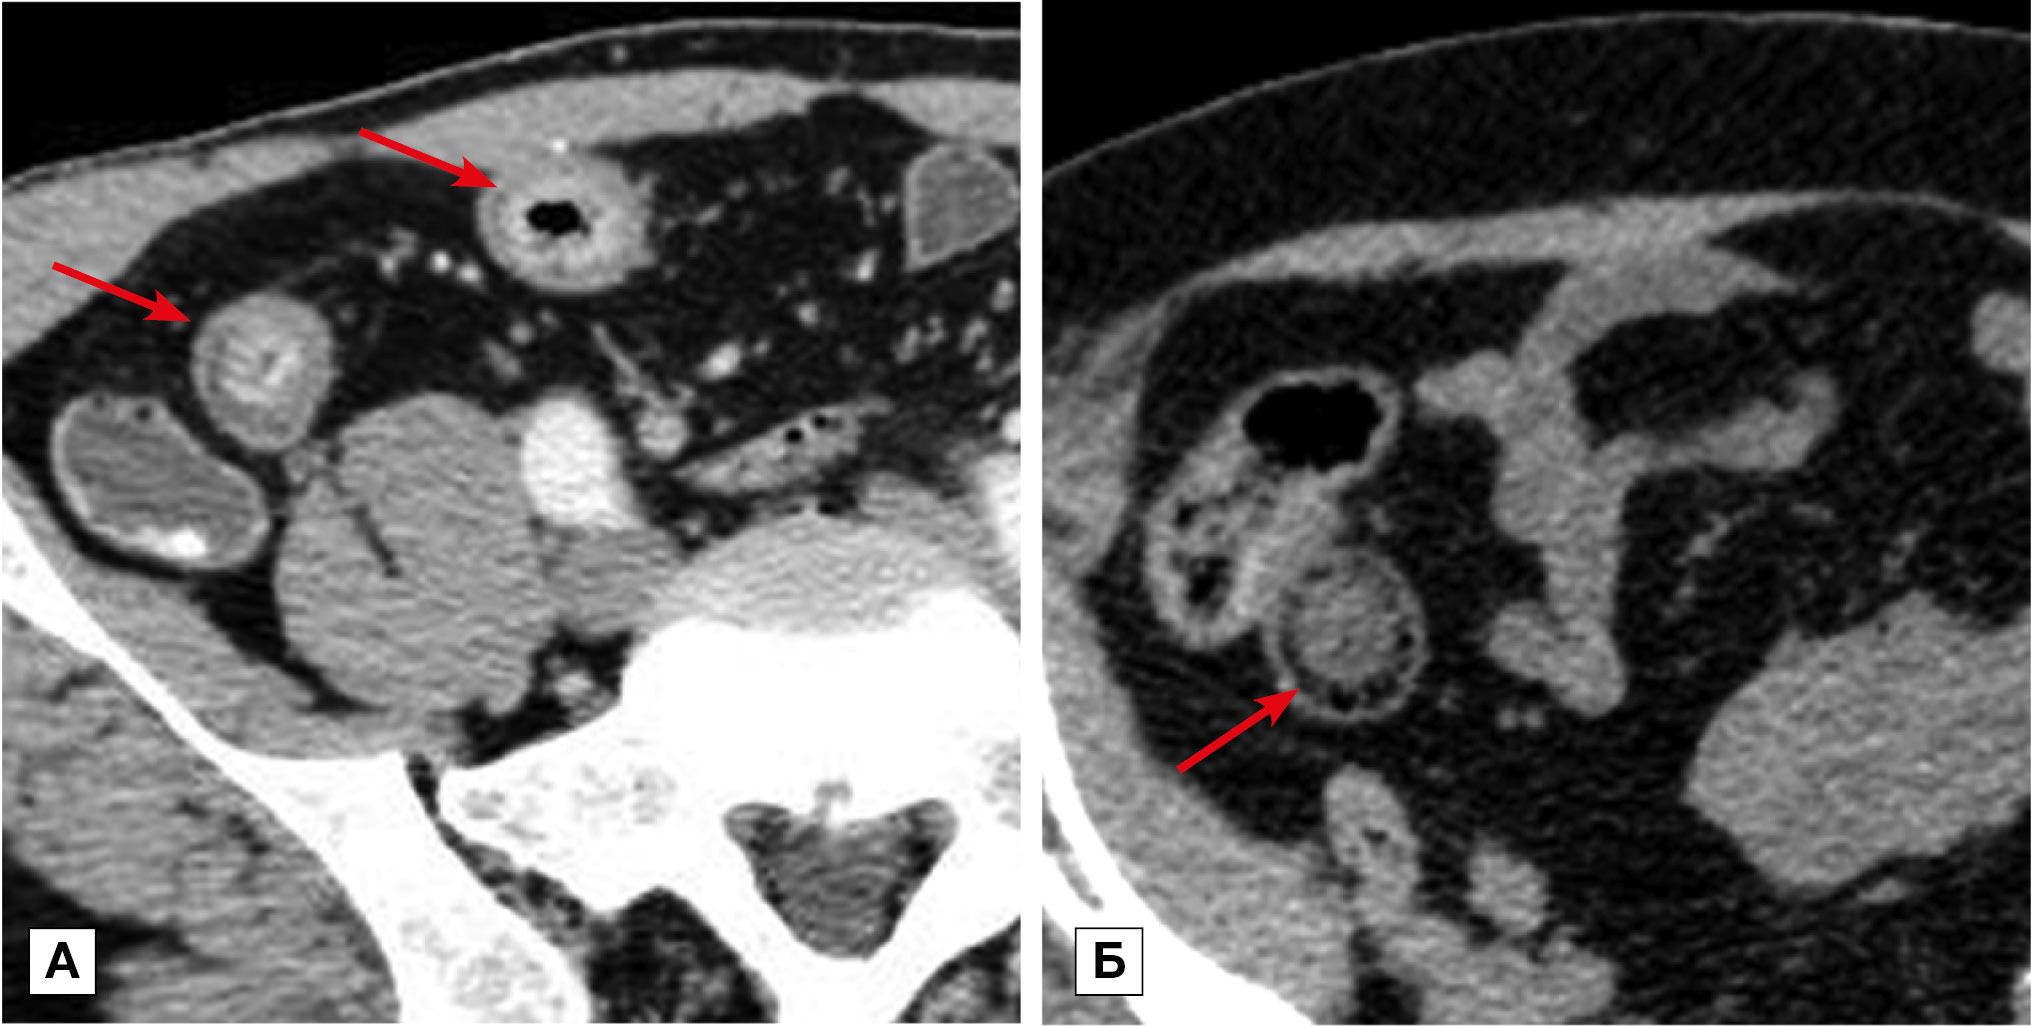

Рис. 9. Больная, 53 года. МСКТ: рак дистального отдела подвздошной кишки. Тонкокишечная непроходимость

Примечание. А — аксиальная томограмма, Б — сагиттальная реконструкция томограммы. Артериальная фаза контрастного усиления. В дистальном отделе подвздошной кишки на протяжении 10 см определяется экзофитное образование, суживающее просвет (стрелки). Опухоль трансмурально накапливает контрастный препарат. В тонком кишечнике имеются признаки компенсированной тонкокишечной непроходимости.

Рис. 10. Больной, 48 лет. МСКТ: саркома подвздошной кишки

Примечание. А — нативное исследование, Б — артериальная фаза контрастного усиления. По брыжеечному краю стенки подвздошной кишки наблюдается сегментарное утолщение стенки (стрелка), которое при контрастном усилении накапливает контрастный препарат равномерно и трансмурально. В прилежащей части брыжейки определяется разрастание элементов опухолевой ткани.

Метастатическое поражение висцеральных листков брюшины вызвало утолщение стенки кишки у 16 (18,6%) больных. Причинами вторичного поражения брюшины чаще служили опухоли желудочно-кишечного тракта и поджелудочной железы. На томограммах метастатическое поражение брюшины проявлялось отложением солидных масс в виде плоскостных или бугристых утолщений на покрывающих кишечник серозных оболочках (рис. 11). При прогрессировании определялась инвазия опухоли в стенку кишки с утолщением стенки и сужением просвета, что вызывало кишечную непроходимость. Поражение чаще носило множественный характер. По протяженности сегментарные утолщения (67%) встречались чаще фокальных (33%), с прогностическим значением положительного результата 20 и 12,2% соответственно. Распространенные поражения сопровождались скоплением жидкости в брюшной полости. При контрастном усилении солидные массы на серозных оболочках характеризовались повышенным контрастным усилением.

Рис. 11. Больная, 68 лет. МСКТ: рак желудка. Метастатическое поражение серозных оболочек. Кишечная непроходимость. Артериальная фаза контрастного усиления

Примечание. В антральном отделе желудка определяется опухоль (пунктирная стрелка). Визуализируются неравномерные утолщения стенки кишки, обусловленные вторичным поражением серозных покровов (стрелки).